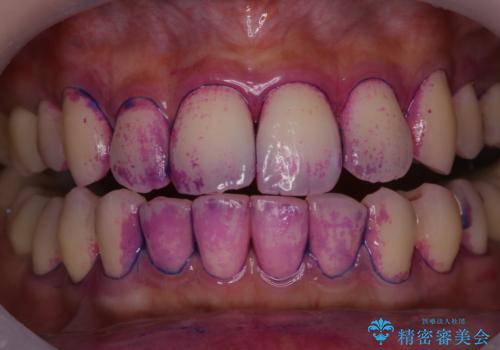

虫歯や歯周病の原因となるプラーク・歯垢(細菌の塊)は、べたべたと歯にくっつきやすく、また歯と同じような色をしているので見落としやすいものです。

虫歯や歯周病の予防のためには、磨き残しやすい場所を染め出し液などで把握しておくことや正確な歯磨き方法を知ることがとても重要です。

綺麗に磨いたつもりでも、歯ブラシが当たりにくい所、苦手な所には、磨き残しがあるものです。